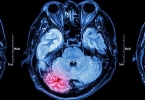

• 40岁脑出血能恢复正常吗

40岁脑出血能恢复正常吗

40岁脑出血患者能否恢复正常主要取决于出血量、损伤部位及康复干预时机,多数患者通过系统治疗可部分或完全恢复功能,主要影响因素包括早期溶栓治疗、血肿清除手术、神经功能康复训练、并发症防控以及心理支持。1、 ...